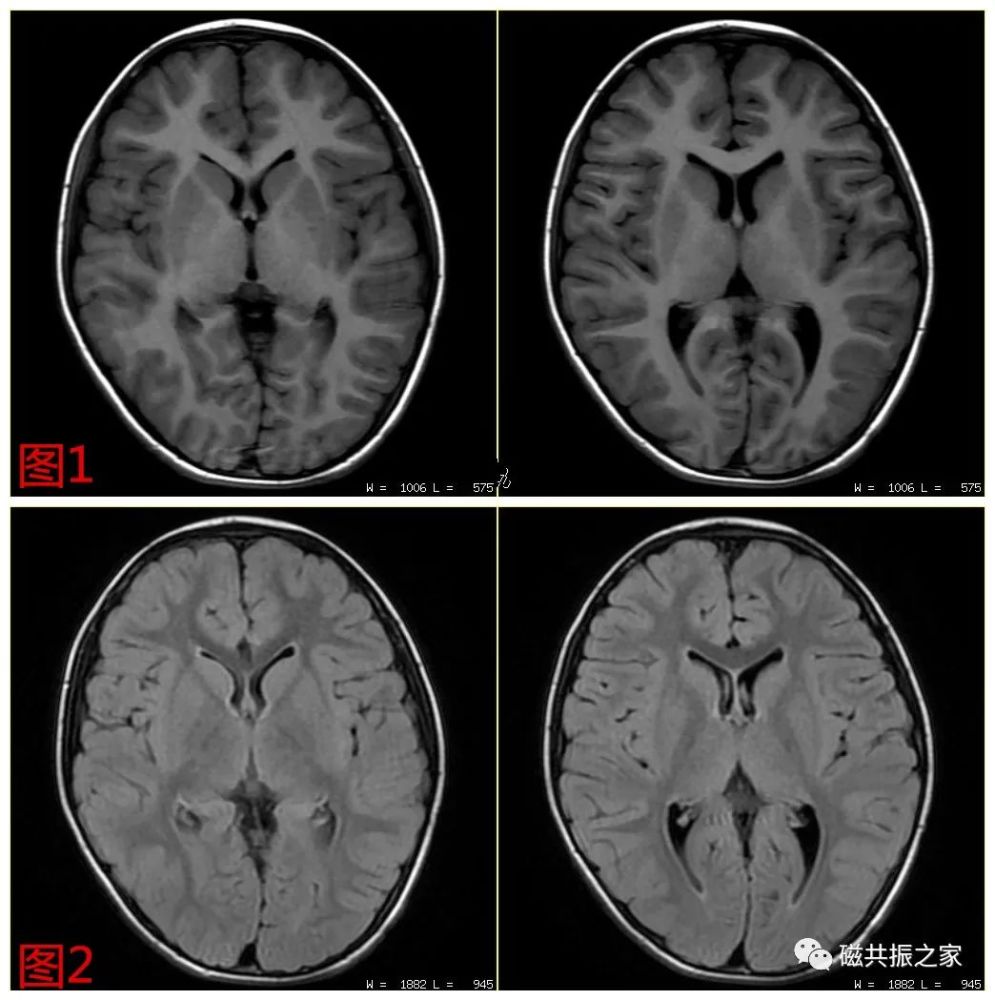

头颅mri入门系列之认识序列

【磁共振基础】让你不再是"权重盲"_腾讯新闻